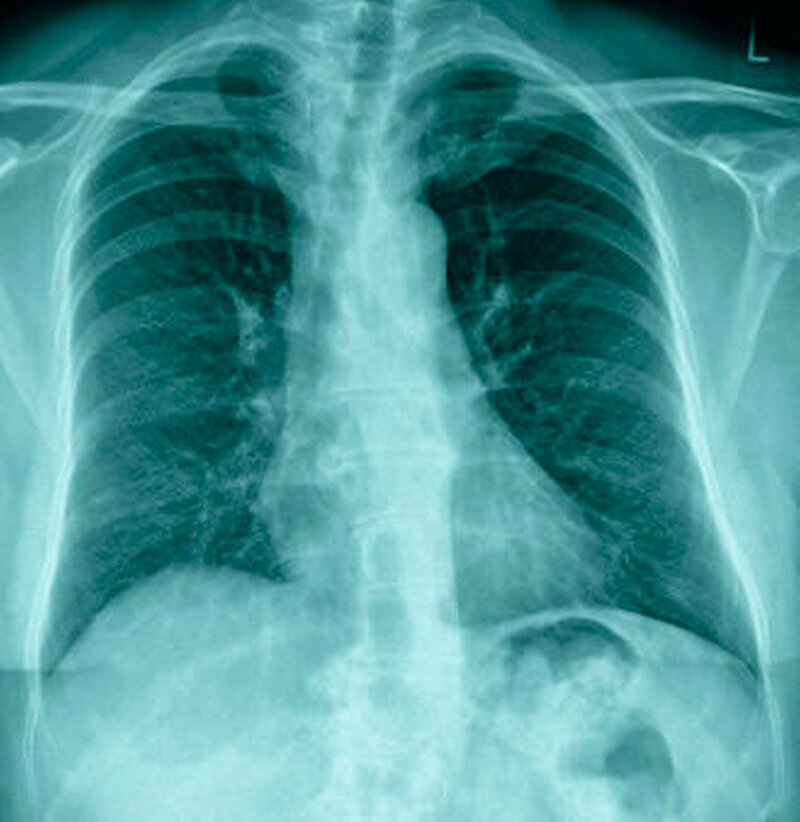

Die histopathologische und weiterführende immunologische Abklärung zur Abgrenzung unter anderem gegenüber einer Tuberkulose erbrachte die Diagnose einer Sarkoidose bei Vorliegen von typischen, nicht verkäsenden, epitheloidzelligen Granulomen. Zur weiteren Abklärung des Erkrankungsstadiums erfolgte eine radiologische Untersuchung der Lunge mittels Röntgen-Thorax und CT, die ohne Nachweis pathologischer Veränderung waren (Abbildung 6).